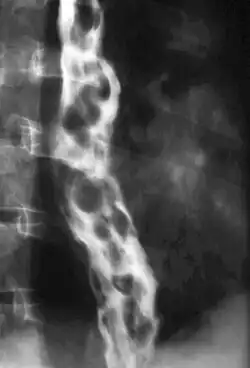

Varizes esofágicas

Varizes esofágicas são dilatações das veias do esôfago. São relacionadas em geral com a cirrosee a esquistossomose e outras doenças que provocam hipertensão da veia porta e podem se romper e provocar hemorragias renais.